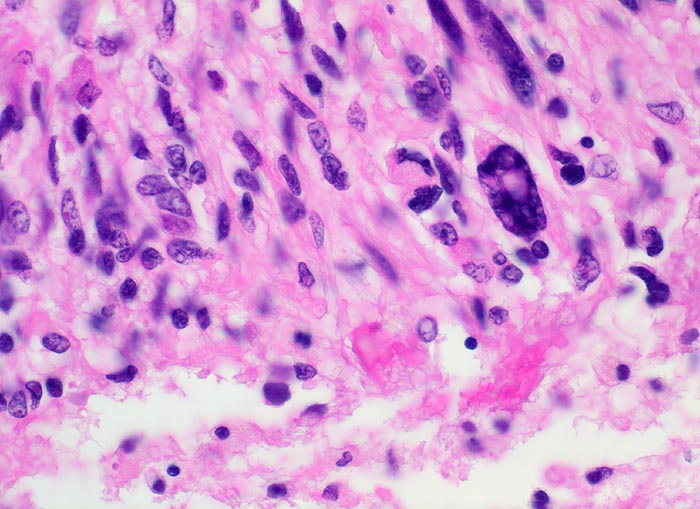

PathoPic – image database / PathoPic ID 5203 - Glioblastoma multiforme (WHO IV)

Glioblastoma multiforme (WHO IV)

maligner Tumor

Hirn temporal

Nervensystem

Hohe Zelldichte, ausgeprägte Kern- und Zellpolymorphie mit hyperchromatischen unregelmässig geformten Zellen.

Seit zwei Monaten zunehmende Persönlichkeitsveränderungen, Kopfschmerzen und progrediente fokal neurologische Zeichen.

Histologie

400

52